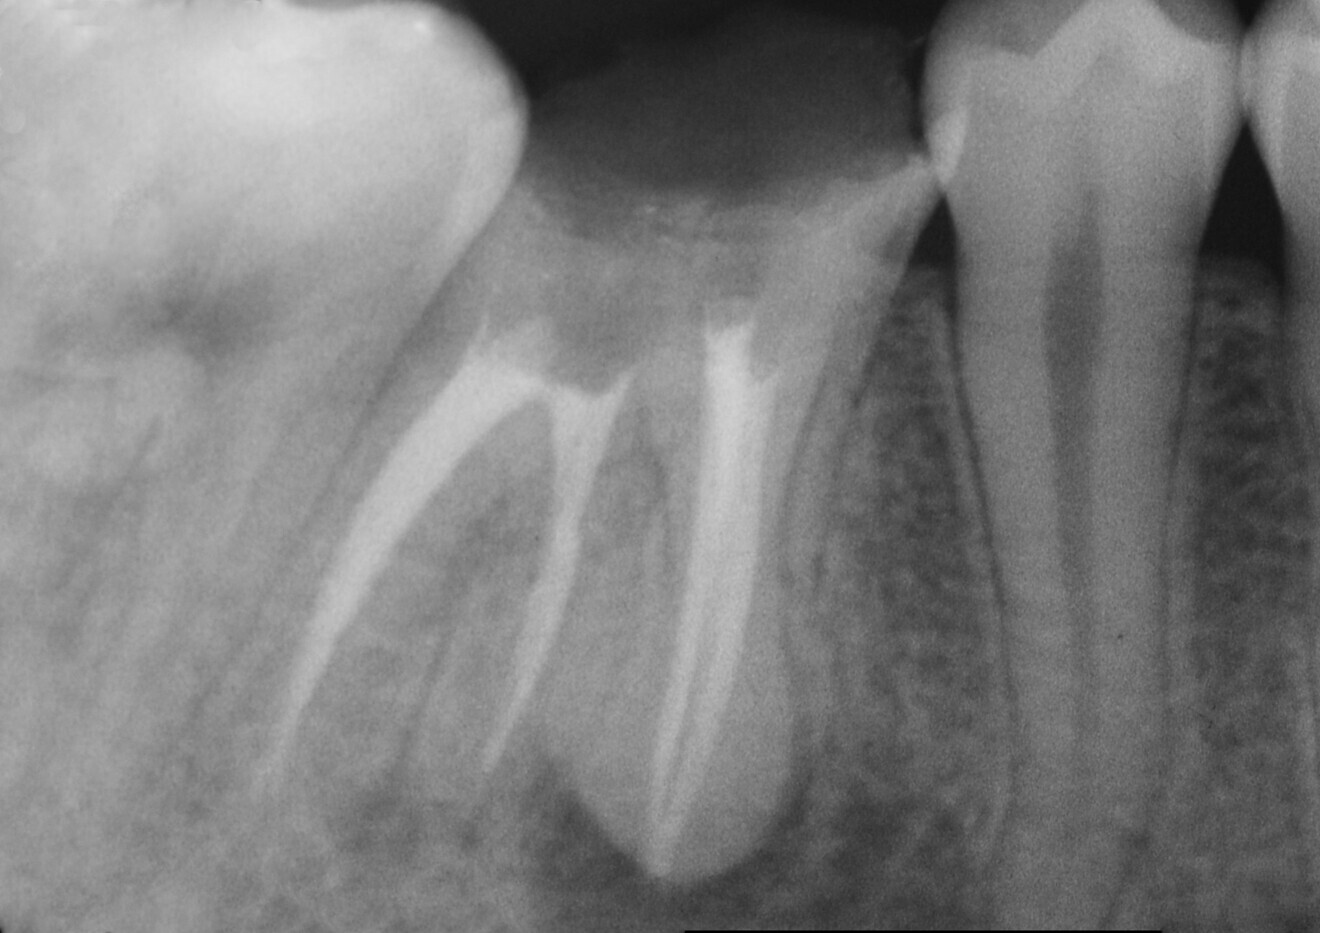

In the radiographic examination, the amalgam restoration showed open margins, especially on the mesial side (Fig. 1). The endodontic treatment was defective: the root canal preparation appeared to have been inadequate, and both the 3D seal and the working length were insufficient. A canal in the distal root seemed not to have undergone any endodontic treatment. Irregular root morphology compatible with hypercementosis was observed in the apical half of the roots of tooth #46, showing an increase of volume of a round shape. A widening of the periodontal space over almost all of its extent could also be observed. A significant apical lesion of the distal root and a smaller one of the mesial root were revealed as well.

The first step was the endodontic reintervention. After local anaesthesia, the operative field was isolated with a dental dam, and a dental dam clamp was placed around tooth #46. The old amalgam was removed, taking care to preserve sound tissue. Once the endodontic filling had been reached, remnants of amalgam and cement were carefully removed. The endodontic filling was removed with rotary instruments for canal shaping and retreatment (ProTaper Universal retreatment files, Dentsply Sirona). The coronal third was treated with the D1 file (30/0.09), the medium third with the D2 file (25/0.08) and the apical third with the D3 file (20/0.07). An entirely mechanical removal procedure was performed to avoid the use of endodontic solvents. The non-treated root canal in the distal root was located and manually prepared with size 15, 20 and 25 K-files. The same files were used for the radiographic check of the working length, which was measured with an apex locator (Fig. 2a).

Once completed, the gutta-percha points were cut manually with a hot instrument. After cleaning the dentine surface of the pulp chamber floor, a radiographic control was carried out (Fig. 3). The results were promising. The radiograph showed properly prepared, well-filled root canals, including the canal in the critical distal root. In all four root canals, the working and filling lengths were now well established.

Fig. 1: Radiograph of the pre-op situation showing insufcient endodontic treatment of tooth #46. Additionally, an amalgam coronal restoration with microleakage was detected. There were also apical lesions evident around both roots. Both neighbouring teeth had migrated towards tooth #46 and closed the interproximal spaces.

Fig. 3: Post-op results of the endodontic treatment. A proper 3D seal had been achieved. The working length and sealing had been corrected. The extra distal root canal had been found, treated and sealed.

Regarding the endodontic retreatment, the preparation and seal of the root canals were appropriate, a suitable 3D seal was achieved and the working length was corrected. Also, the previously untreated root canal in the distal root was properly prepared and sealed (Fig. 23).